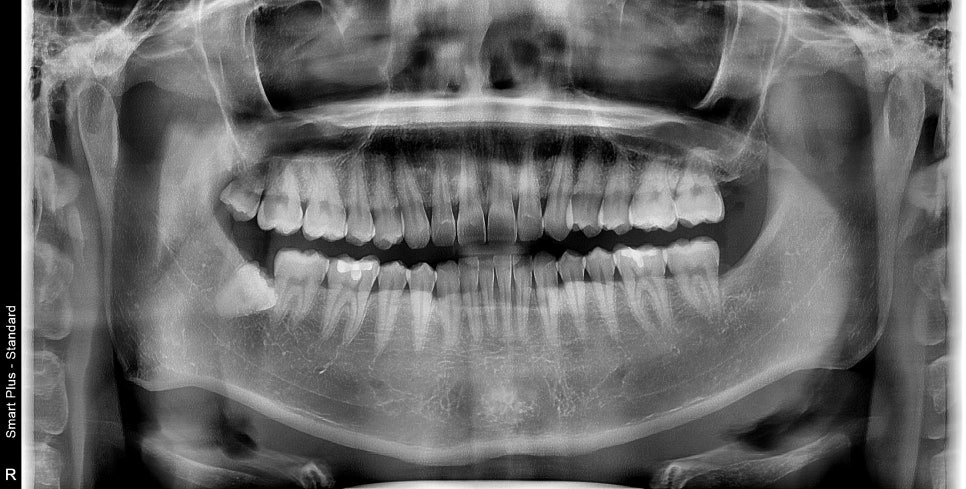

일단 약을 먼저 드시고, 증상 완화 후 발치를 시작했습니다.

완전히 매복되어 있고 입이 잘 벌어지지 않으셔서

시야 확보에 애를 먹었지만

위아래 2개의 사랑니가 잘 발치가 되었습니다.

초기 치유도 좋으셨고,

오랜만에 정기점검을 오셔서 체크 겸 엑스레이를 찍어보았습니다.

발치 주변이 깔끔하게 치유가 된 것을 볼 수 있습니다.

저렇게 사랑니가 누워서 옆에 치아와 붙어있는 경우에는

사랑니 발치 후 옆 치아 뿌리가 노출이 될 수 있기 때문에

잇몸 치유가 느린 경우 노출된 부위가 시릴 수 있습니다.

이 환자분은 증상도 별로 없으셨고,

발치 당시 지혈, 압박이 잘되어 초기 잇몸 치유 상태가

좋았던 걸로 기억이 됩니다.